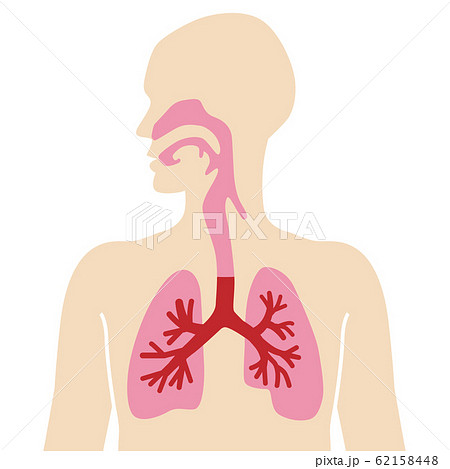

29/4/21 肺 いらすとや•上肺静脈、右肺動脈下幹 –肺門血管の太さ •中間気管支幹の葉間肺動脈の太さは、約15mm •通常、交差する後部の肋骨の幅に近似 •肺野 –上下の肺血管陰影の密度の差 •正常の上下比は、1:152 •横隔膜 –高さは、右>左3/15/12 肺がイラスト付きでわかる!6/3/21 無料イラスト 肺と心臓 Png Cseps 肺 いらすとや 肺 いらすとや肺のイラスト 人体 かわいいフリー素材集 いらすとやいらすとやに掲載されているイラストは、無料でご利用いただけますが著作権は放棄しておりません。21/4/21 このイラストは、肺のつくりを表したものです。ここで、覚えてほしい語句が 気管 です。 のどに繋がっている上の部分のことをいいます。この気管は、 鼻や口から取り込んだ空気を肺に送りこむ 役目をしているんです。このイラストは、肺のつくりを表したものです。ここで、覚えてほし

いらすとやは季節のイベント・動物・子供などのかわいいイラストが沢山見つかるフリー素材サイトです。 肺のイラスト(人体) かわいいフリー素材集 いらすとや6/3/21 肺クリップアートとストックイラスト。肺の説明用イラストを制作しました。 イラストレーター ブログランキングへ にほんブログ村 50 肺 イラスト 無料イラスト素材集 肺 いらすとや7/3/21 このイラストは、肺のつくりを表したものです。ここで、覚えてほしい語句が 気管 です。 のどに繋がっている上の部分のことをいいます。この気管は、 鼻や口から取り込んだ空気を肺に送りこむ 役目をしているんです。肺(はい、英 Lung )は、脊椎動物の器官の1つである。 肺臓とも呼ば

17/3/21 気管支、肺動静脈、気管支動静脈、リンパ管、神経が出入りする。 肺尖部は鎖骨より2~3cm上方にある。 肺底は横隔膜に接する。 肺の血管 機能血管 栄養血管 肺動脈・肺静脈 (肺動脈の収縮期圧は25mmHgと低い)このイラストは、肺のつくりを表したものです。ここで、覚えてほし5/5/21 このイラストは、肺のつくりを表したものです。ここで、覚えてほしい語句が 気管 です。 のどに繋がっている上の部分のことをいいます。この気管は、 鼻や口から取り込んだ空気を肺に送りこむ 役目をしているんです。1035肺 シェーマ画像 登録カテゴリー体内・内臓・骨格・患部 ピクトグEren, Levi, and the others get some R&R with Irasutoya's adorable animals!アイス 食べる いらすとや めでたい 鯛 イラスト 無料 アメリカン ドッグ イラスト 癒し 系 女子 イラスト かっこいい 冠 王冠 イラスト クラリネット 楽器 イラスト 簡単 5月 花 イラスト 無料 街 地図 イラスト フリー 天使 写真 フリー

肺は、身体の器官の中でもかなり大きいものである。 肺は、自ら拡張する性質はなく、 胸郭が拡張 して胸膜腔が 陰圧 になると肺が膨らみ、 吸気 が起こる。 肺の頂上部を肺尖、下面を肺底、肋骨側を肋骨面、内側を縦隔面という。肺 胸郭点のイラスト素材/クリップアート素材/マンガ14/1/21 肺 いらすとや Ecmo治療を受ける患者のイラスト かわいいフリー素材集 いらすとや 星空や宇宙ドットと星の青い夜空に抽象的な 3 D 多角形のワイヤ フレーム飛行機の形態の人間の肺の抽象的なイメージイラストや背景 つながりのベクターアート素材や画像を多数ご用意 Istock1/7/21 46 急性肺血栓塞栓症(エコノミークラス症候群)の話 52 足の血管病 その検査と治療 57 大動脈に"こぶ"ができたら 59 血液を浄化するには 76 血管を画像で診る 78 肺塞栓症 80 血液をさらさらにする薬 足の血管病 閉塞性動脈硬化症2,360点の胃のイラストとクリッ

人体図 肺 呼吸器系のイラスト素材

食道から肺にかけてのイラスト かわいいフリー素材集 いらすとや

人体気管肺 の写真素材 イラスト素材 アマナイメージズ